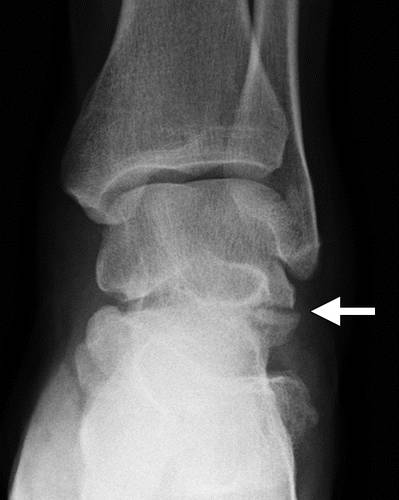

这种损伤必须与三角骨 - 一个附件后骨小梁区分开来。 在放射照相术中,后过程的断裂显示不规则的边缘(图13),而三角骨是圆形或椭圆形,具有光滑的皮质边缘(图14)。 双侧X线照片的价值有限,因为据报道三分之二的病例是双侧的(32)。 如果射线照片不确定,应进行CT。

图13b后突骨折。 (a)右足的外侧X光片显示在距骨后方的小骨质碎片(箭头)。 (b)右脚的轴向CT图像显示后路过程骨折(箭头)以及粉碎的程度和程度。